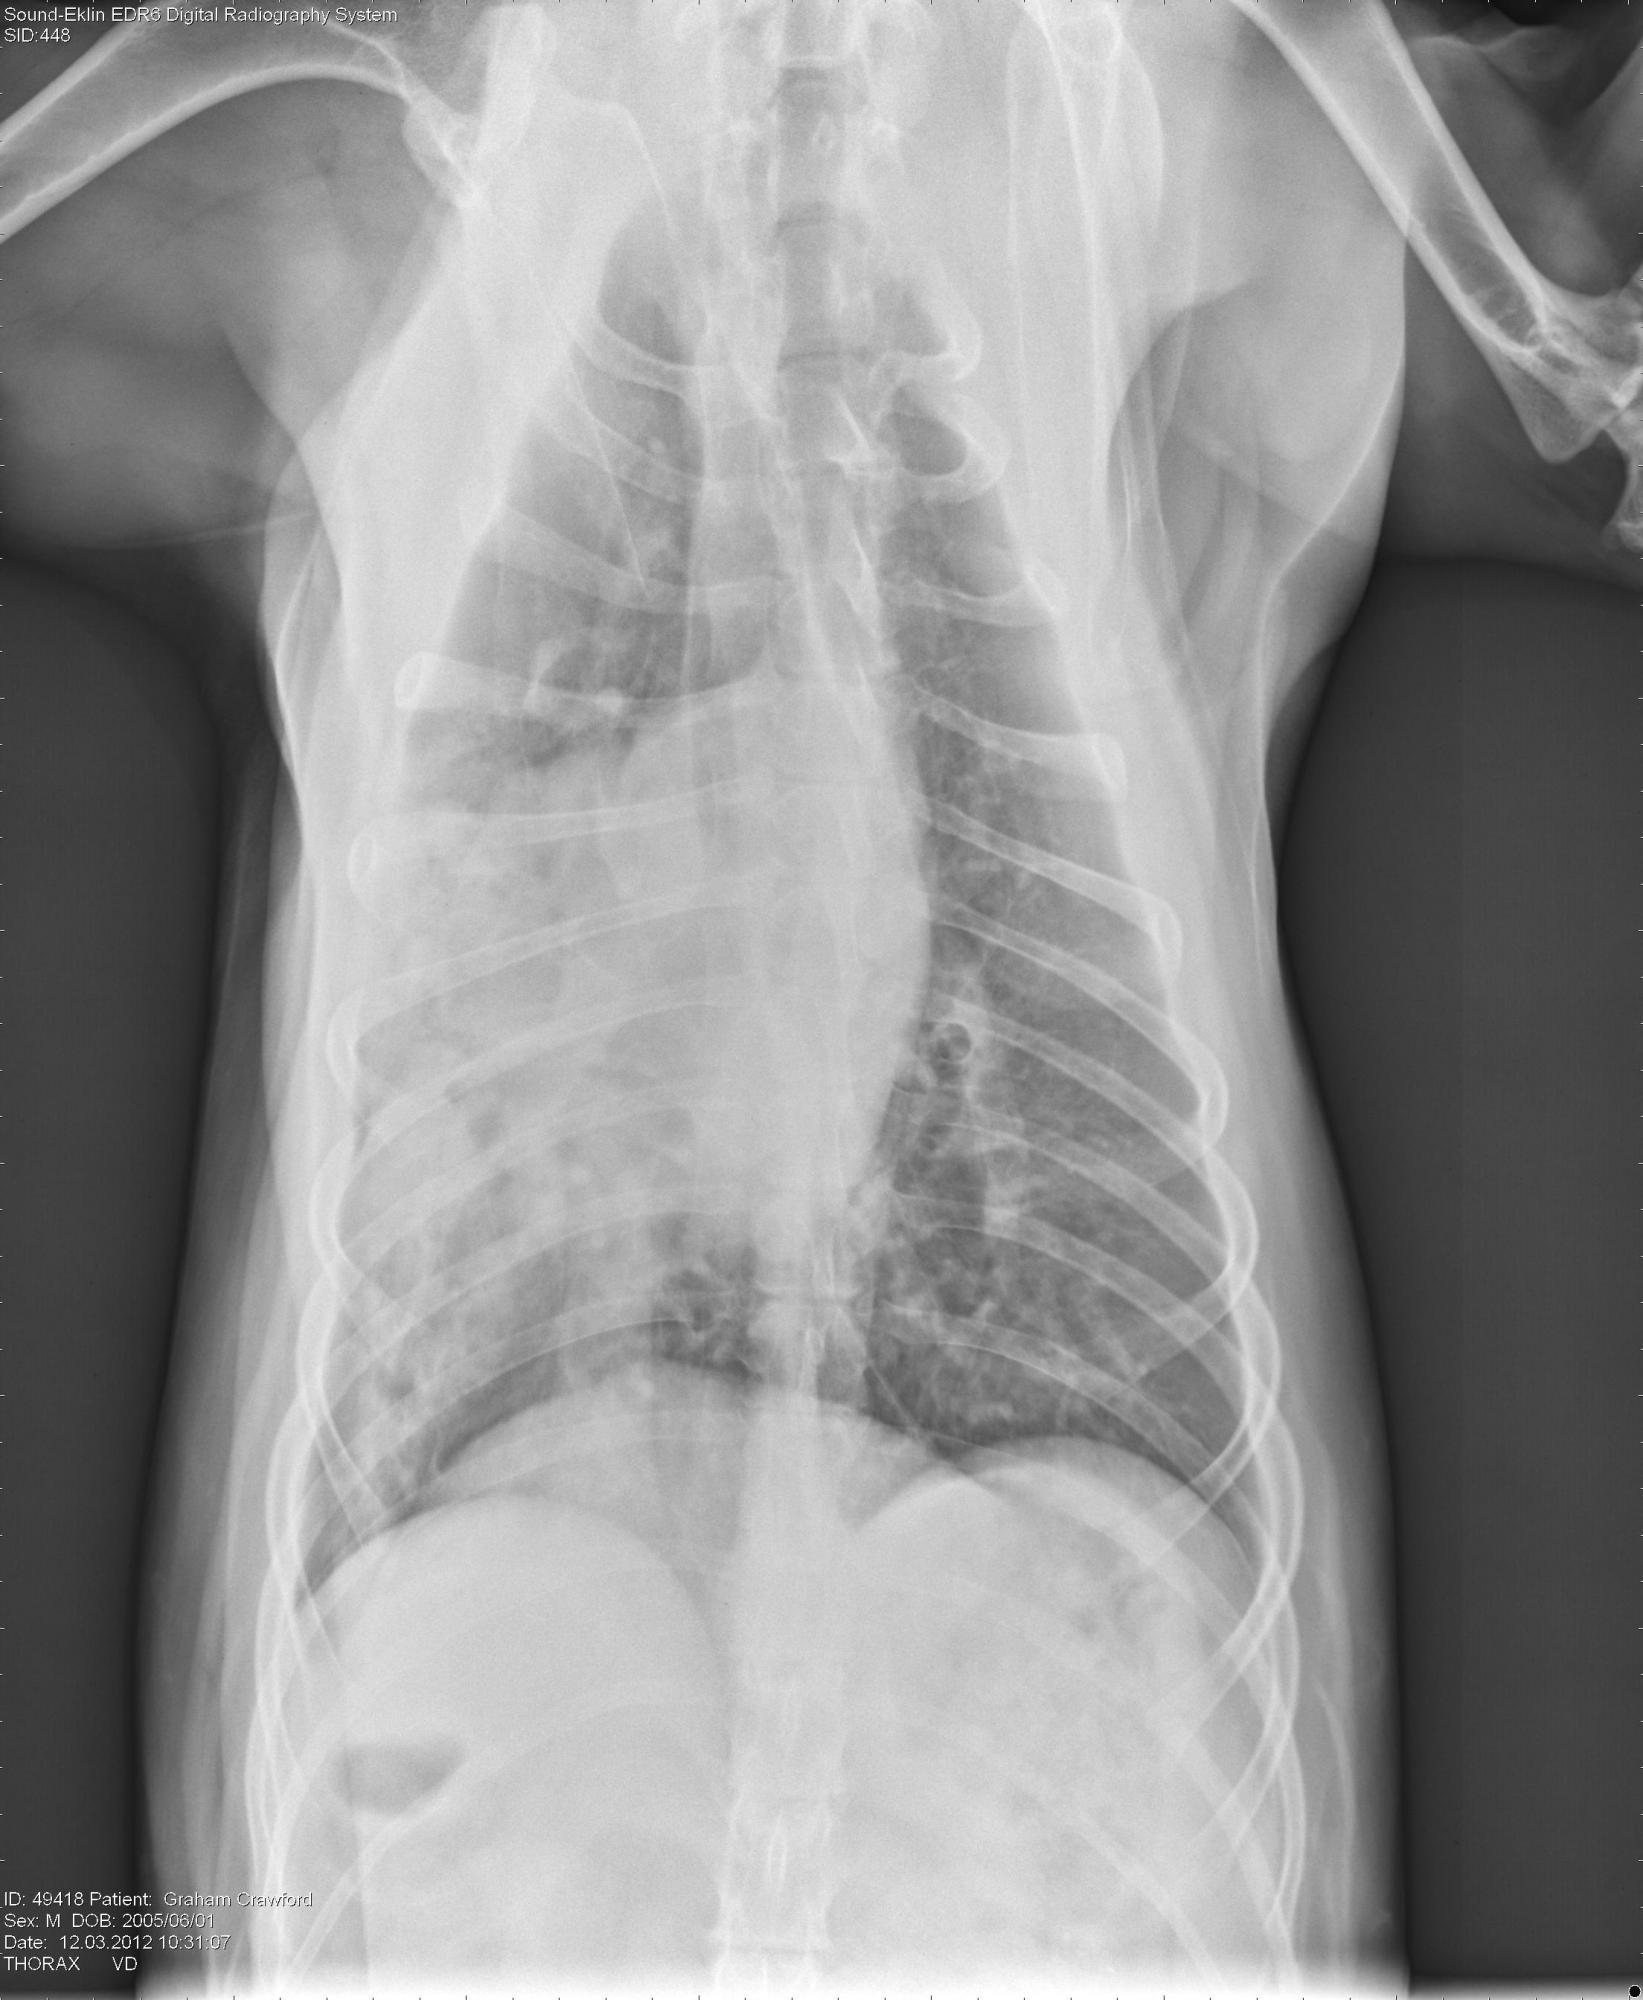

The following radiographs are from a 9 year old Golden Retriever with history of heart base tumor treated with pericardectomy 6 months ago. There is a current history of acute onset of an episode of vomiting yesterday with acute onset of dyspnea today.

What is your diagnosis?

The diagnosis is pneumonia ;) It is not always cancer :)